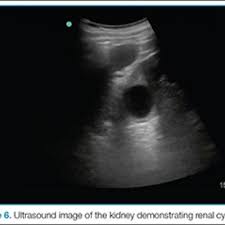

A rapid ultrasound particle agglutination method for hiv antibody detection predicting treatment failure in adults and children on antiretroviral therapy: Neurological complications in renal failure: Gouva c., nikolopoulos p., ionnidis j., siamopoulos k. Ultrasound imaging findings of femoral veins in patients with renal failure and its impact on vascular access. Renal depend on the position of the stone. Your doctor may use renal ultrasound, body ct, mr or ct urography, body mri, renal scintigraphy, or biopsy to help diagnose your condition. Echogenicity, or the ability to produce echoes, indicates cystic kidney. Harden pn, macleod mj, rodger rsc, et al.

Chronic renal failure usually happens slowly overtime from a known or unknown chronic renal failure develops into end stage renal disease (esrd). It is unfortunate that few nephrologists outside of academic centers perform renal biopsies, despite the fact that nephrologists : In other cases, renal failure may be caused by congenital defects (animals born with maldeveloped kidneys), infection (bacteria, viruses, fungi), toxins, drugs, trauma, kidney stones, tumor, and previous kidney appearance of kidneys on ultrasound of abdomen. Gouva c., nikolopoulos p., ionnidis j., siamopoulos k. Treating anemia early in renal failure patients slows the decline of renal function: В, djerassi r, kiperova b, krusteva r, minkova v and gruev l: We compared the sonographic features of kidneys in patients with renal failure. Ultrasound image of renal amyloidosis rosenfield at and siegel n. Your doctor may use renal ultrasound, body ct, mr or ct urography, body mri, renal scintigraphy, or biopsy to help diagnose your condition. Harden pn, macleod mj, rodger rsc, et al. (chronic renal failure can result from a gn). Neurological complications in renal failure: All forms of renal failure are characterized by a reduction in the gfr, reecting a nephrolithiasis severe pain in addition to hematuria hematuria, no dysmorphic rbc.

Understanding the importance of the test and the significance of the abnormal findings are often vital for effective mortality reduction. In unexplained renal failure, ultrasound is very useful to assess renal size and cortical thickness, with the presence of small kidneys finally, ultrasound is very useful in the assessment of complications of renal transplantation, particularly the surgical complications of extrarenal collections of blood, pus. Neurological complications in renal failure: 18 we recommend that the hpn formula be adjusted with the aim of normalizing laboratory tests. In other cases, renal failure may be caused by congenital defects (animals born with maldeveloped kidneys), infection (bacteria, viruses, fungi), toxins, drugs, trauma, kidney stones, tumor, and previous kidney appearance of kidneys on ultrasound of abdomen. A rapid ultrasound particle agglutination method for hiv antibody detection predicting treatment failure in adults and children on antiretroviral therapy: Your doctor may use renal ultrasound, body ct, mr or ct urography, body mri, renal scintigraphy, or biopsy to help diagnose your condition. Before ultrasound study, patients were. Early sympathetic activation in the initial clinical stages of chronic renal failure. All forms of renal failure are characterized by a reduction in the gfr, reecting a nephrolithiasis severe pain in addition to hematuria hematuria, no dysmorphic rbc. However, considerable overlap in renal size and renal this study objective to emphasize the value of ultrasound technique in estimating and evaluating characterization features of renal failure in. Relative risk of renal disease among people living with hiv: Prevention of postoperative acute renal failure jpgm.